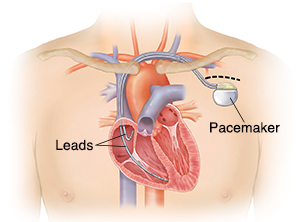

Overview

Package includes:

Days in hospital : 4 Days (For patient and one attendant)

Days in hotel : 10 Days (For patient and one attendant)

Room type in hospital : Shared

Room type in hotel : Private

Hotel category: Standard

Value added benefits of the Pacemaker Procedure Biventricular:

Ø Doctor consultation charges

Ø Lab tests and diagnostic charges

Ø Room charges inside hospital during the procedure

Ø Surgeon Fee

Ø Nursing charges

Ø Hospital surgery suite charges

Ø Anesthesia charges

Ø Routine medicines and routine consumables (bandages, dressings etc.)

Ø Food and Beverages inside hospital stay for patient and one attendant.

Extra benefits:

ü Interpreter

ü Visa assistance

Ø Site tourism of the city

Ø Follow up with the doctor

Ø Airport pick up and drop

Ø Free online consultation with the doctor

Ø Priority appointments with the doctor

Ø Room upgrade from sharing to private

Overview

Package includes:

Days in hospital : 1 to 2 Days (For patient and one attendant)

Days in hotel : 5 Days (For patient and one attendant)

Room type in hospital : Shared

Room type in hotel : Private

Hotel category: Standard

Value added benefits of the Pacemaker Procedure Double Chamber:

Ø Doctor consultation charges

Ø Lab tests and diagnostic charges

Ø Room charges inside hospital during the procedure

Ø Surgeon Fee

Ø Nursing charges

Ø Hospital surgery suite charges

Ø Anesthesia charges

Ø Routine medicines and routine consumables (bandages, dressings etc.)

Ø Food and Beverages inside hospital stay for patient and one attendant.

Extra benefits:

ü Interpreter

ü Visa assistance

Ø Site tourism of the city

Ø Follow up with the doctor

Ø Airport pick up and drop

Ø Free online consultation with the doctor

Ø Priority appointments with the doctor

Ø Room upgrade from sharing to private

Overview

Package includes:

Days in hospital : 3 to 4 Days (For patient and one attendant)

Days in hotel : 8 Days (For patient and one attendant)

Room type in hospital : Shared

Room type in hotel : Private

Hotel category: Standard

Value added benefits of the Permanent Pacemaker Implantation:

Ø Doctor consultation charges

Ø Lab tests and diagnostic charges

Ø Room charges inside hospital during the procedure

Ø Surgeon Fee

Ø Nursing charges

Ø Hospital surgery suite charges

Ø Anesthesia charges

Ø Routine medicines and routine consumables (bandages, dressings etc.)

Ø Food and Beverages inside hospital stay for patient and one attendant.

Extra benefits:

ü Interpreter

ü Visa assistance

Ø Site tourism of the city

Ø Follow up with the doctor

Ø Airport pick up and drop

Ø Free online consultation with the doctor

Ø Priority appointments with the doctor

Ø Room upgrade from sharing to private